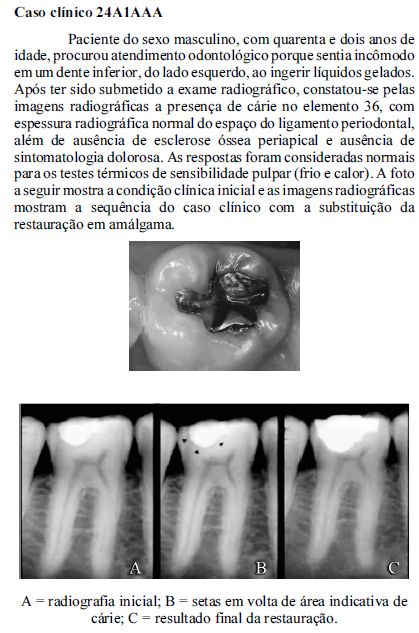

A radiolucidez da imagem bidimensional, que permite a visualização da presença de cárie sob a restauração, conforme mostrado na imagem A, deve-se à densidade da lesão cariosa, à passagem do feixe com pouca ou nenhuma resistência e à absorção de altas quantidades de raios X.

O comprimento da onda e dos tempos de exposição aos raios X e de revelação são fatores que determinam a variação de densidade óptica e o contraste e a densidade do objeto, como mostram as imagens A, B e C.

Apesar das variações anatômicas individuais, a radiopacidade da restauração metálica mostrada na imagem C se deve ao elevado número atômico desse objeto.Paciente de quinze anos de idade, do sexo feminino, compareceu ao consultório odontológico com dor intensa e aumento volumétrico moderado da face direita. Após exame clínico simples, foi constatado que havia uma cárie extensa no primeiro molar inferior direito. A paciente relatou ser alérgica à penicilina.